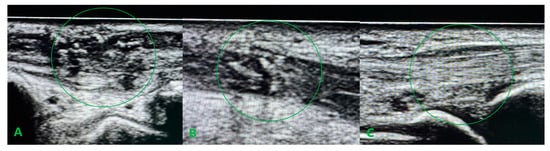

Figure 5.

Longitudinal ultrasound sections of the reconstructed tendons six weeks after surgery confirming the efficacy of the distal Pulvertaft sutures. APL (A), ECRL (B), and ECRB (C). The most suitable ultrasound graft integration for ECRB tendon.

In our case, the repair of the damaged retinaculum consisted of creating two separate canals in the surrounding scar tissue at the spot of the second and third anatomical compartments to ensure good graft adhesion without conflict during sliding motion. This approach stays in line with Kawakatsu M. et al. reports, which emphasized that it is important to reconstruct only the extensor retinaculum, not the entire sliding surface [10]. Unlike the case described by the above authors, our patient did not require further tenolysis, probably because we introduced gentle passive movements from the third week after surgery. We avoided the necessity to release adhesions, which can also be explained by the fact that intraoperatively, during radical passive flexion and extension of the hand at the level of the reconstructed retinaculum, only the PL graft was sliding beneath without conflict with the level of suturing. A considerable issue during tendon reconstructive procedures is determining the appropriate graft tension. In the case of isolated extensor reconstruction, techniques for estimating graft tension are known, such as those described by Kamoi F. et al., who treated 20 patients with EPL damage with good results [11]. They assumed that the tension of the reconstructed EPL should be adjusted so that the center of the distal edge of the thumbnail is elevated 2 cm above the operation table. The situation is much more complex in the case of multiple tendon reconstruction. In our patient, the tension of the ECRB and ECRL grafts was determined to achieve a neutral hand position in both the flexion/extension and the ulnar/radial deviation plane. The tension of the APL graft was an intraoperative dilemma, which was sewn in with minimal tension, not guided by the position of the thumb. This may translate into afterward problems with rehabilitation in thumb opposition. Postoperative rehabilitation for extensor tendon damage in zones V to VII has historically relied on the immobilization of the hand for 4 to 6 weeks after surgery. From the literature, in zones V to VII, complications can arise with tendon adhesions, joint contracture, prolonged rehabilitation, and limitations of hand function. Extensor tendon rehabilitation providing passive or dynamically assisted sliding of the reconstructed tendon, the same as an actively mediated extension, significantly improves the quality of results compared to static splinting [8,12,13,14]. In our case, the introduction of the passive wrist and hand movements from the third week after surgery assisted active extension from the fifth week after surgery, and the patient’s involvement in the rehabilitation process resulted in a very good functional outcome. Ultrasound examination (UE) should focus on assessing early results and detecting complications, mainly tendon adhesions. UE also allows for managing rehabilitation progress and assessing the sliding movement of the repaired tendon or tendon graft. In our case, UE was used to confirm the sliding movement of the PL grafts during passive extension movements at the early rehabilitation stage and to exclude splitting of the tendon ends.